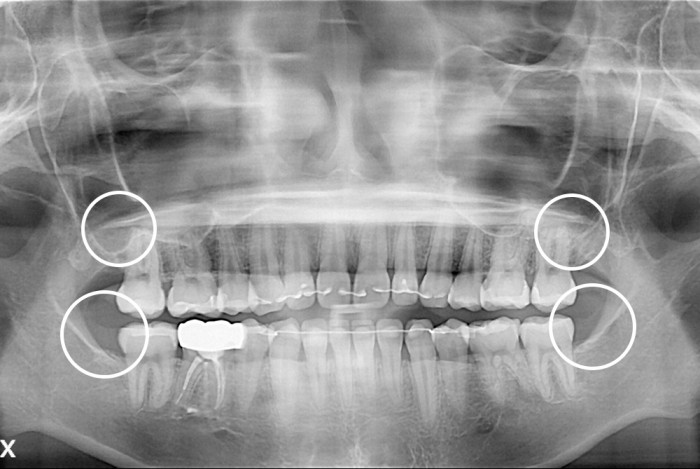

치료후 : 2021-06-05

세종치과는 구강악안면외과학 박사이신 원장님이 발치하는 치과입니다.